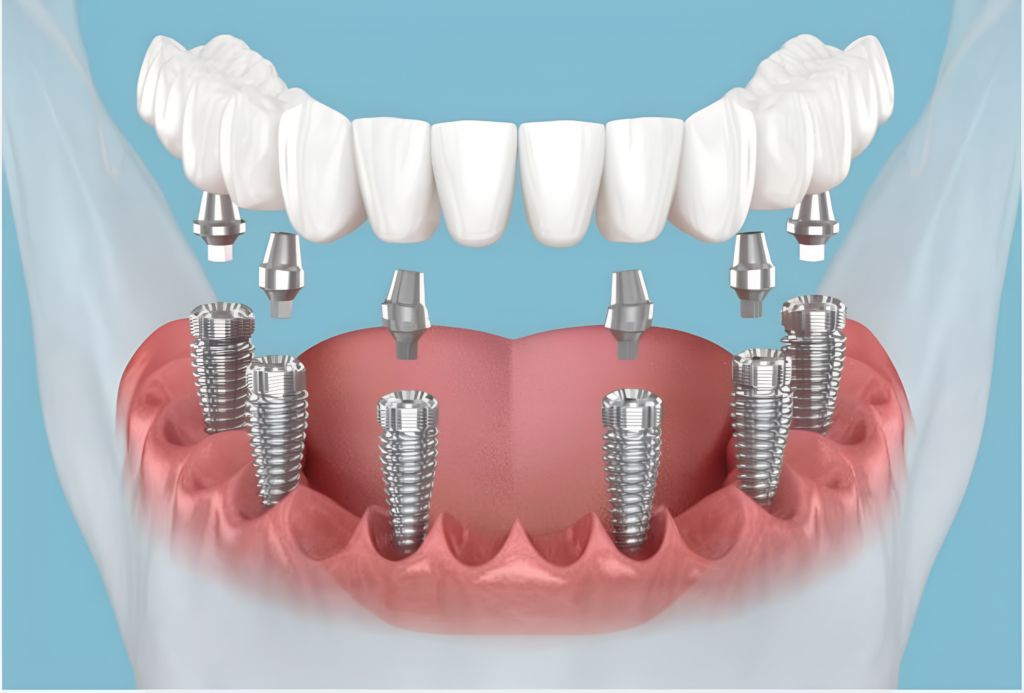

Implantes de Carga Imediata

Dentes fixos em até 15 dias, sem enxerto e com cirurgia minimamente invasiva. O tratamento definitivo para quem usa dentadura ou perdeu dentes.

Prótese Fixa sobre Implantes

Substituímos sua dentadura por uma prótese fixa, firme e natural. Você mastiga o que quiser, sorri com confiança e esquece que um dia usou dentadura.